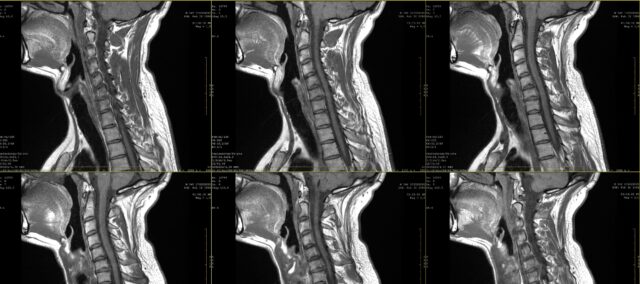

La școală, ați învățat cu siguranță despre desenele pentru durerea radiculară. Cu toate acestea, deja în primul deceniu al secolului XXI, a devenit clar că durerea radiculară nu urmează neapărat o distribuție dermatomală. Acest studiu a dorit să analizeze mai atent concordanța dintre inspecția vizuală a desenelor de durere radiculară observate de pacienți și RMN. În practică, un pacient își exprimă adesea plângerile și acestea pot fi completate cu un desen al durerii. Atunci când se suspectează o durere radiculară, deseori se prescrie imagistica medicală pentru a determina rădăcina nervoasă afectată și gradul de afectare a posibilei rădăcini nervoase. Deși acest lucru face, în multe cazuri, parte din practica de rutină, nu știm până când nu cunoaștem acordul dintre aceste desene de durere și rădăcina nervoasă afectată, determinată cu ajutorul RMN. În acest studiu, Marco et al. (2023) au comparat desenele durerii radiculare și rezultatele RMN.

Pentru a investiga acordul dintre desenele durerii radiculare și rezultatele RMN, acest studiu a inclus participanți cu o istorie de 2 luni de durere persistentă, care au fost diagnosticați cu radiculopatie cervicală la RMN. Acest diagnostic a fost pus de un neurochirurg pe baza informațiilor clinice și a constatărilor RMN evaluate de un radiolog.